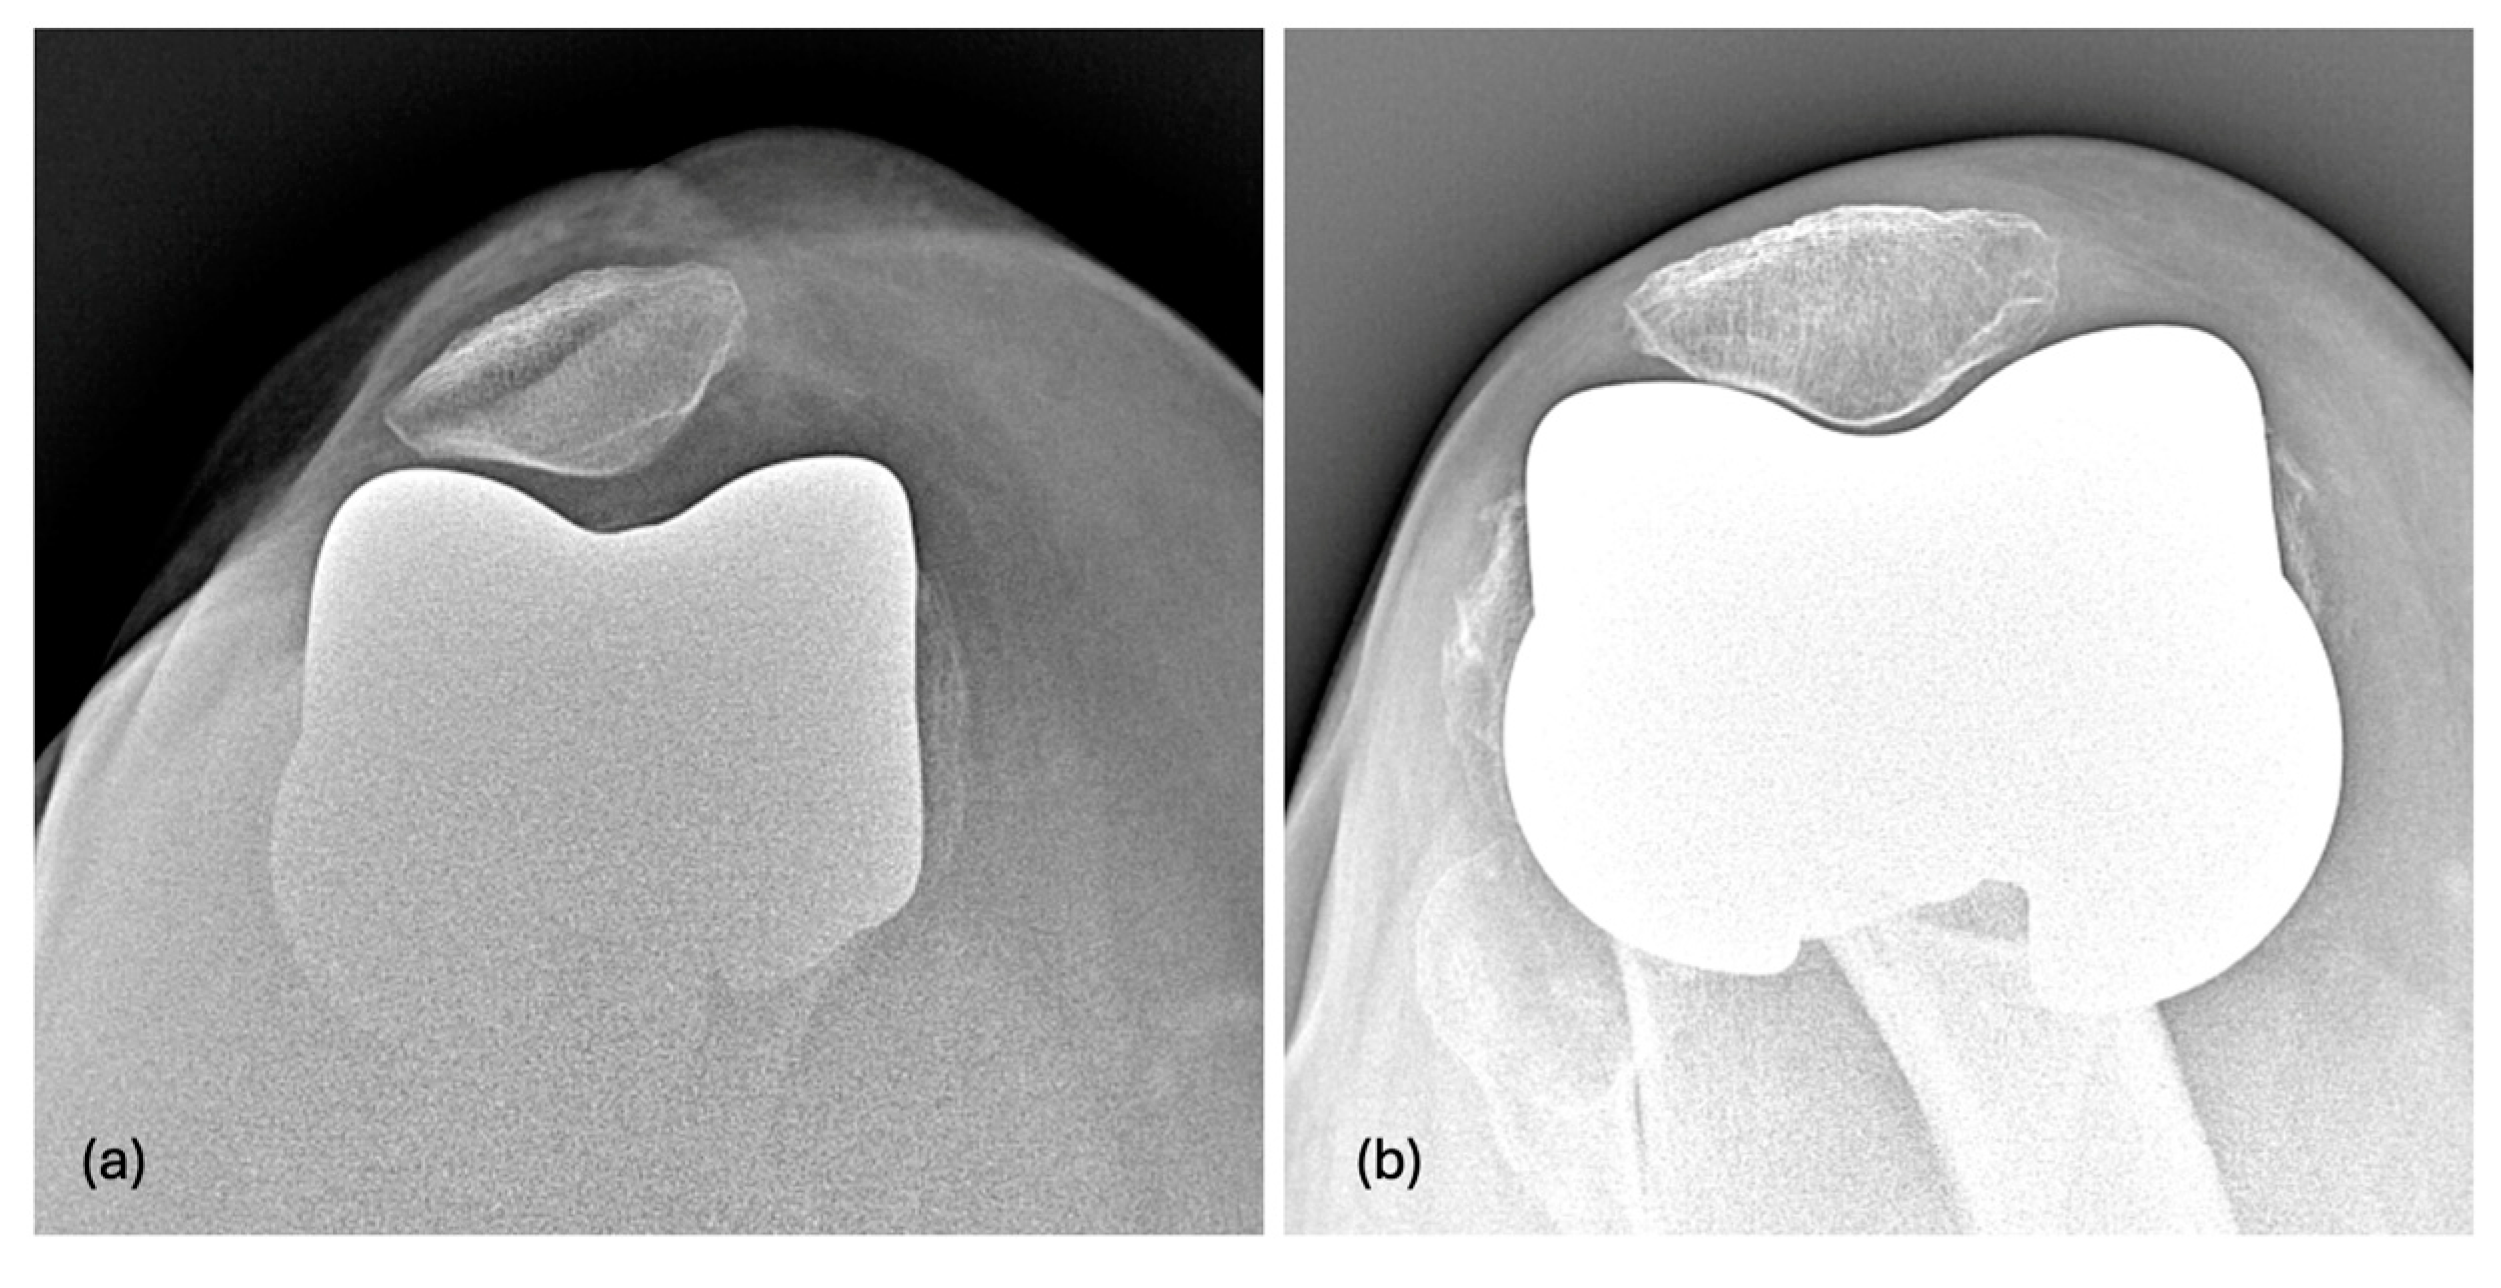

2.4. Postoperative Radiographic Measure